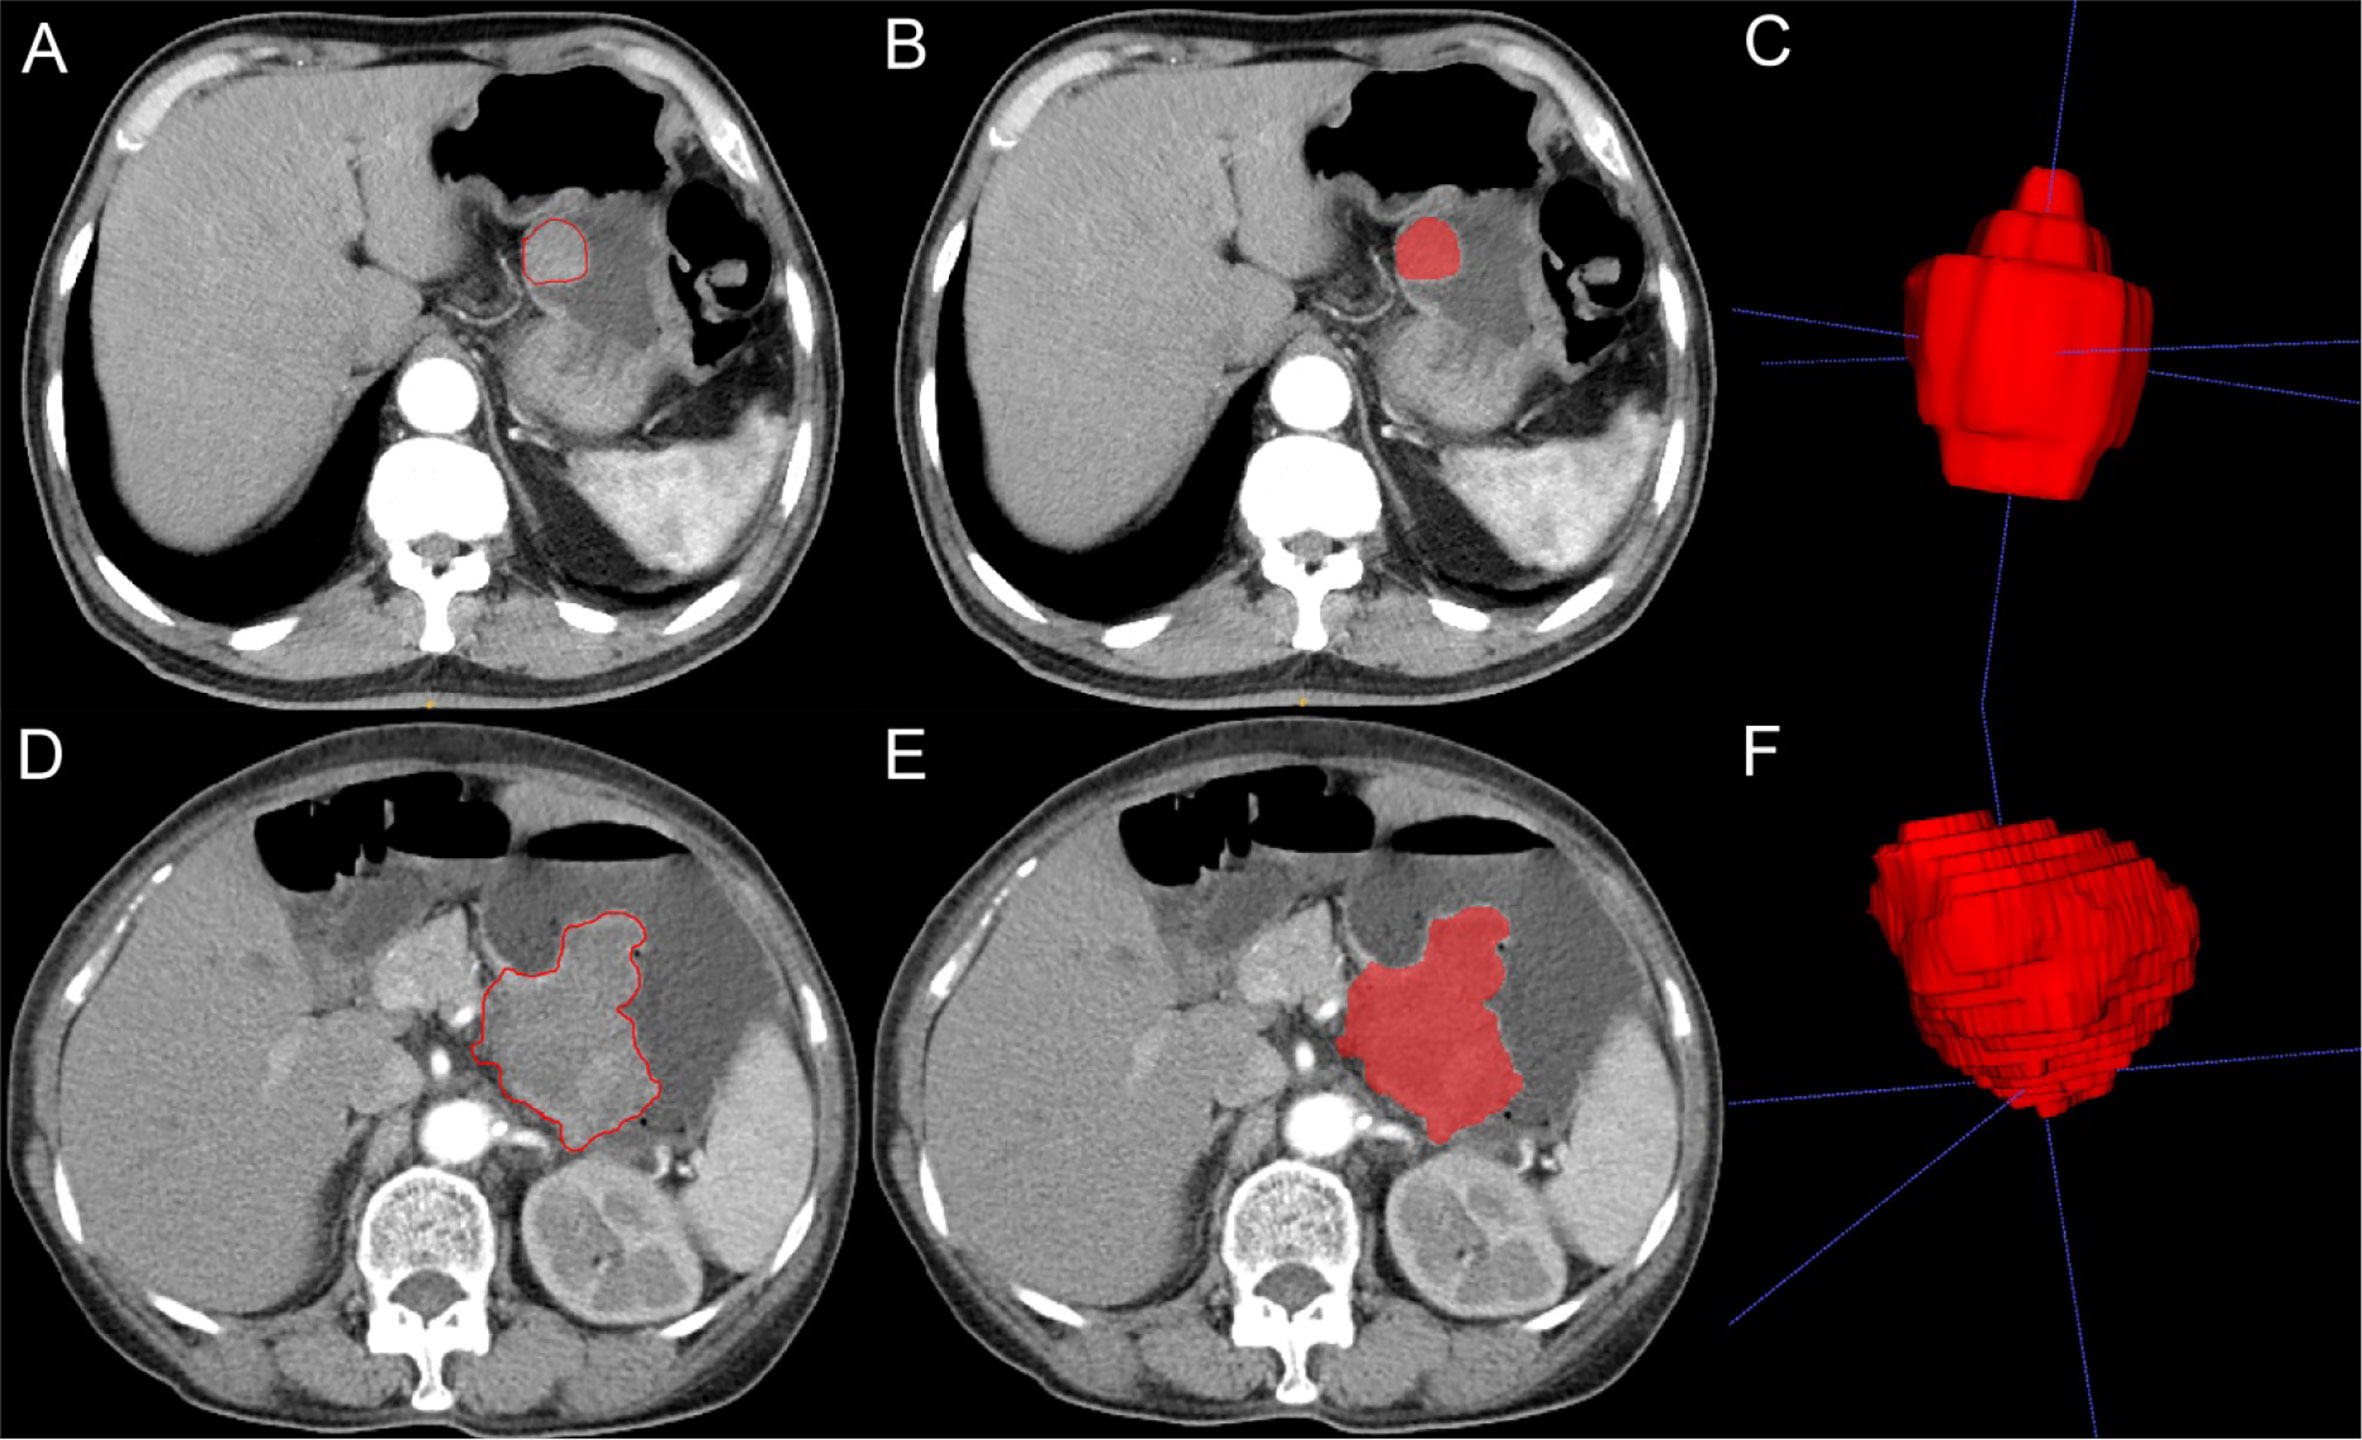

Two radiologists (physicians 1 and 2) with 10 years of experience in the abdominal imaging diagnosis applied the ITK-SNAP software (version 3.8.0, https://www.itksnap.org) to delineate the CT-enhanced images at the arterial and venous phases. The delineated areas included the tumor lesion as much as possible without inclusion of the surrounding normal tissues or other tissues in order to generate a two-dimensional (2D) region of interest (ROI) (Figure 2). The 2D ROI was then recombined to generate a 3D volume of interest (VOI) for subsequent image feature extraction and analysis.

Figure 2 Imaging segmentation of gastrointestinal stromal tumors (GIST) on computed tomography (CT) imaging. (A) Two-dimensional (2D) CT arterial phase image of potential malignant GIST. The tumor is quasicircular and uniformly enhanced. The red outline is the boundary drawn by radiologists to show the tumor. (B) 2D segmentation of the tumor. (C) 3D segmentation of the tumor lesion. (D) 2D CT arterial phase image of malignant GIST with irregular shape and uneven internal enhancement of the tumor. The red outline is the boundary drawn by radiologists to show the tumor lesion. (E) 2D segmentation of the tumor. (F) 3D segmentation of the tumor.